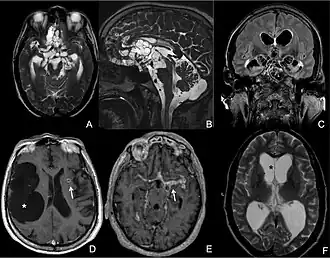

MRI of extraparenchymal neurocysticercosis

Different presentation patterns of extraparenchymal neurocysticercosis as revealed by brain MRI[36]

CT scans and magnetic resonance imaging (MRI) give objective information about the number and pattern of lesions, the stage of healing, and how the immune system is responding to the parasites.[19] MRIs are better for evaluating different spatial planes and provides clearer images, which helps in identifying small lesions at the back of the brain or near the skull that may be missed on CT scans. CT scans are more sensitive at detecting calcium buildup in the brain due to its ability detect calcifications in the brain.[30]

Live vesicular cysts are small, round lesions with little swelling around them and do not need contrast for imaging. The tapeworm head (scolex) usually appears as an asymmetric nodule inside the cysts. Multiple live cysts with these heads corroborate the diagnosis. Once the cysts begin to break down (colloid cysts), their borders become unclear, they are surrounded by swelling and exhibit significant ring or nodular contrast enhancement. Calcified cysticerci are shown on CT scans as non-enhancing hyperdense nodules without swelling.[20]